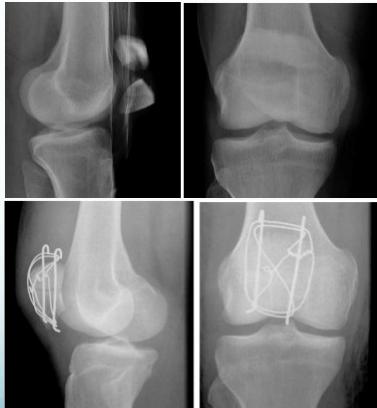

Tension-band Wires

- Indications:

- Patellar and olecranon fractures

- Possible to use in malleolar fractures

- Application:

- K-wires applied first, then tension-band wire